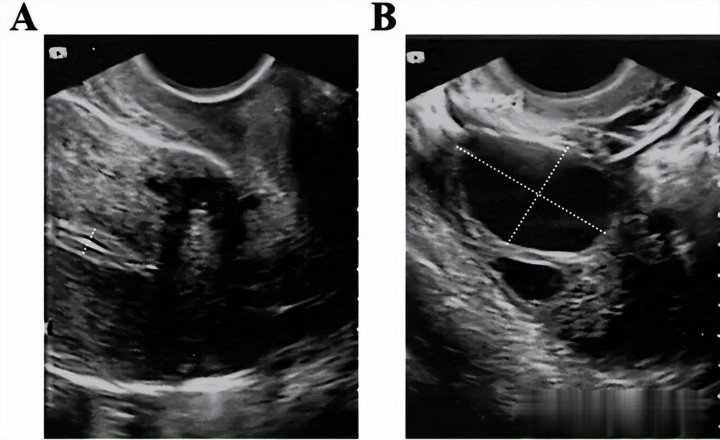

2023年5月11日,患者移植一枚4bb级囊胚,移植14天血清hcg水平为1065mIU/ml。 移植后30天,超声可见胎心后,停用戊酸雌二醇及黄体酮打针液,孕10周时停用黄体酮阴谈缓释凝胶,地屈孕酮片减量至每周一次,直至孕12周。